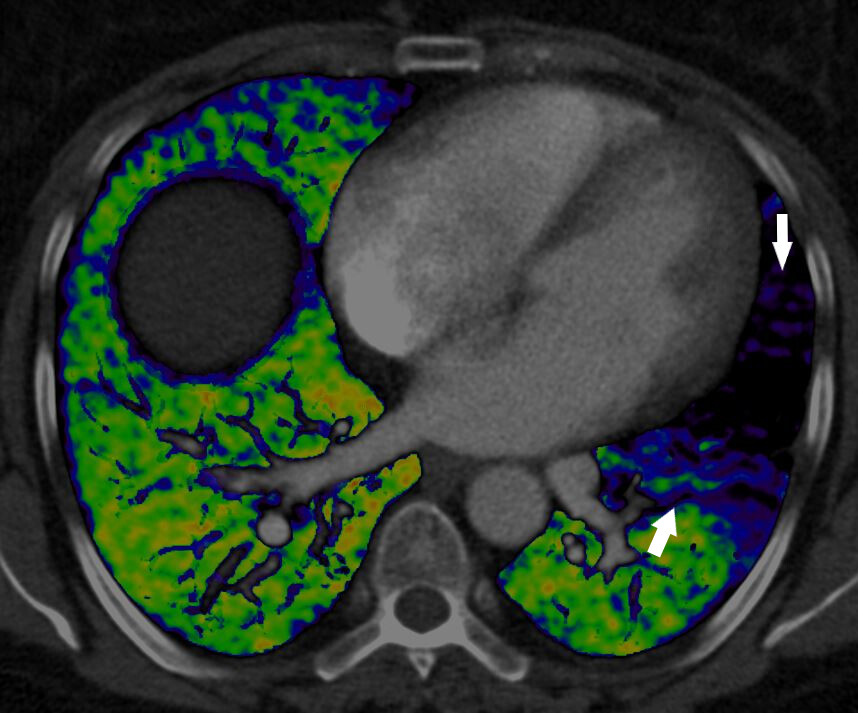

“At Royal Brompton and Harefield Hospitals we have expertise in dual-energy CT pulmonary angiography which is a specialist diagnostic tool which accurately diagnoses the presence, location and extent of a pulmonary embolism. This technique helps develop the best treatment strategy and has been particularly useful in the case of high-risk pulmonary embolism.”

Dual energy CT is an emerging technology that combines two X-ray beams to predict the function of the lung’s blood vessels. This image demonstrates the effect of a blood clot in the left lung which is preventing blood from reaching the lungs (arrows) and as a result, preventing the oxygenation of blood in this part of the lung. The normal lung is well supplied by blood vessels (shown in green).